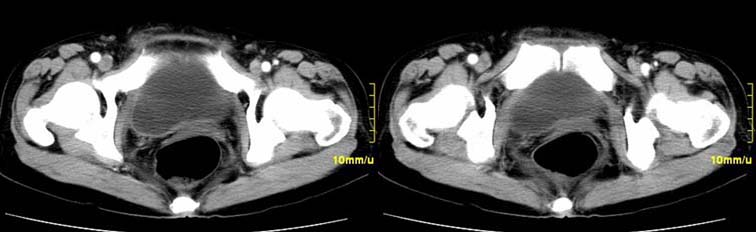

患者,52,右下腹疼痛一月,当时有发热,抗炎治疗20余天,至今仍疼痛,且有低热。

右附件区软组织包块,内可见坏死,边界不清,周围软组织及脂肪组织可见密度增高,膀胱右侧壁增厚,并且呈膨胀不全的改变,考虑炎性包裹,不知道有没有手术史??

右侧附件见一肿块,边缘与周围组织分界不清,增强扫描见肿块明显强化,越到后期强化越明显,中央见坏死,内壁光整,与临近子宫壁、直肠及膀胱后壁均见炎症波及。这种厚壁肿块、内缘光整外缘模糊、增强扫描强化越后越强是附件脓肿典型的ct表现。

右侧卵巢输卵管慢性脓肿,炎症波及临近子宫、直肠及膀胱形成粘连。

右附件区软组织包块,内可见坏死,边界不清,周围软组织及脂肪组织可见密度增高,膀胱右侧壁增厚,并且呈膨胀不全的改变,考虑炎性包裹